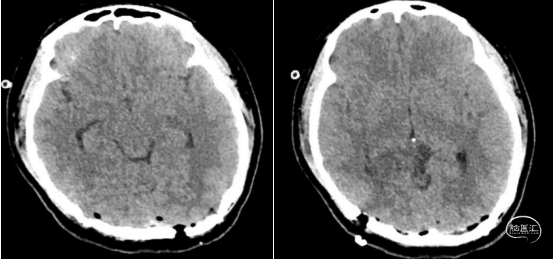

术后

术后管理要点:严密监测神经系统症状,密切观察患者头痛缓解情况、发热等。术中血性或者炎性脑脊液容易出现三脑室底、中脑导水管部分黏连或者堵塞形成梗阻性脑积水,需要定期复查,制定后续治疗综合方案,若仍不能缓解者则需要手术治疗。

本例患者影像学上表现为累及胼胝体压部的典型的蝴蝶状胶质瘤,病变累及双侧半球,非对称分布。手术均用右侧顶枕叶造瘘+左侧纵裂入路,术中先后探查和分块切除大脑镰后部两侧的病变。大脑镰后部毗邻大脑深部静脉系统,需要尽可能避免损伤Galen静脉或下矢状窦等重要结构,左侧纵裂入路可能有利于实现更好的功能保护。位于胼胝体不同部位的蝴蝶状肿瘤,由于解剖基础和功能保护的需求,采取不同的入路,从而在尽可能保护脑功能的前提下安全切除病变。